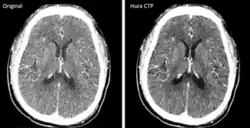

The development and FDA clearance of photon-counting detectors (PCD) for computed tomography (CT) scans in 2022 was an important innovation. These detectors offer a more efficient process for converting X-rays to electrical signals, allowing for better material differentiation and potentially reducing the radiation dose for patients. The image to the right shows two scans of the same brain using old and new CT technology respectively.[24]